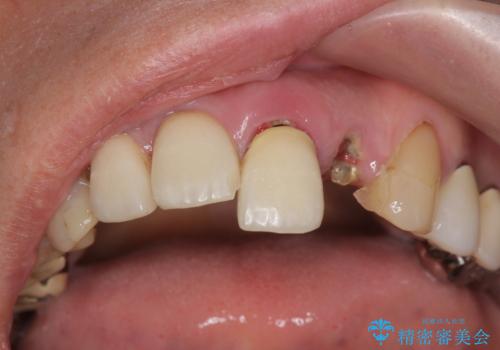

- 歩行中に躓いて転倒し、前歯2本がグラグラになってしまい痛み・審美性の改善を求めて来院されました。

X線検査・視診より強くぶつけた前歯は折れてしまい、抜歯が必要な状況です。

抜歯後の見た目改善として深い咬合関係であることからインプラントは避け、ブリッジで補綴治療を行っていくこととしました。

元々の噛み合わせが深く(ディープバイト)、転んで顎を強打したことで上顎前歯2本が根元から折れてしまい抜歯をしなければいけない状況となってしまいました。